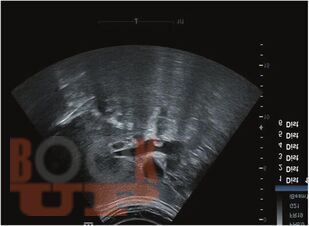

Интервенционные методы диагностики и лечения осложнений желчнокаменной болезни

В учебном пособии изложены актуальные данные о современных интервенционных методах диагностики и лечения осложнений желчнокаменной болезни [на основе данных клинических рекомендаций «Желчнокаменная болезнь – 2024-2025-2026» (2024 г.), которые официально применяются с 01.01.2025 г. в соответствии с Постановлением Правительства РФ от 12.07.2022 № 393].